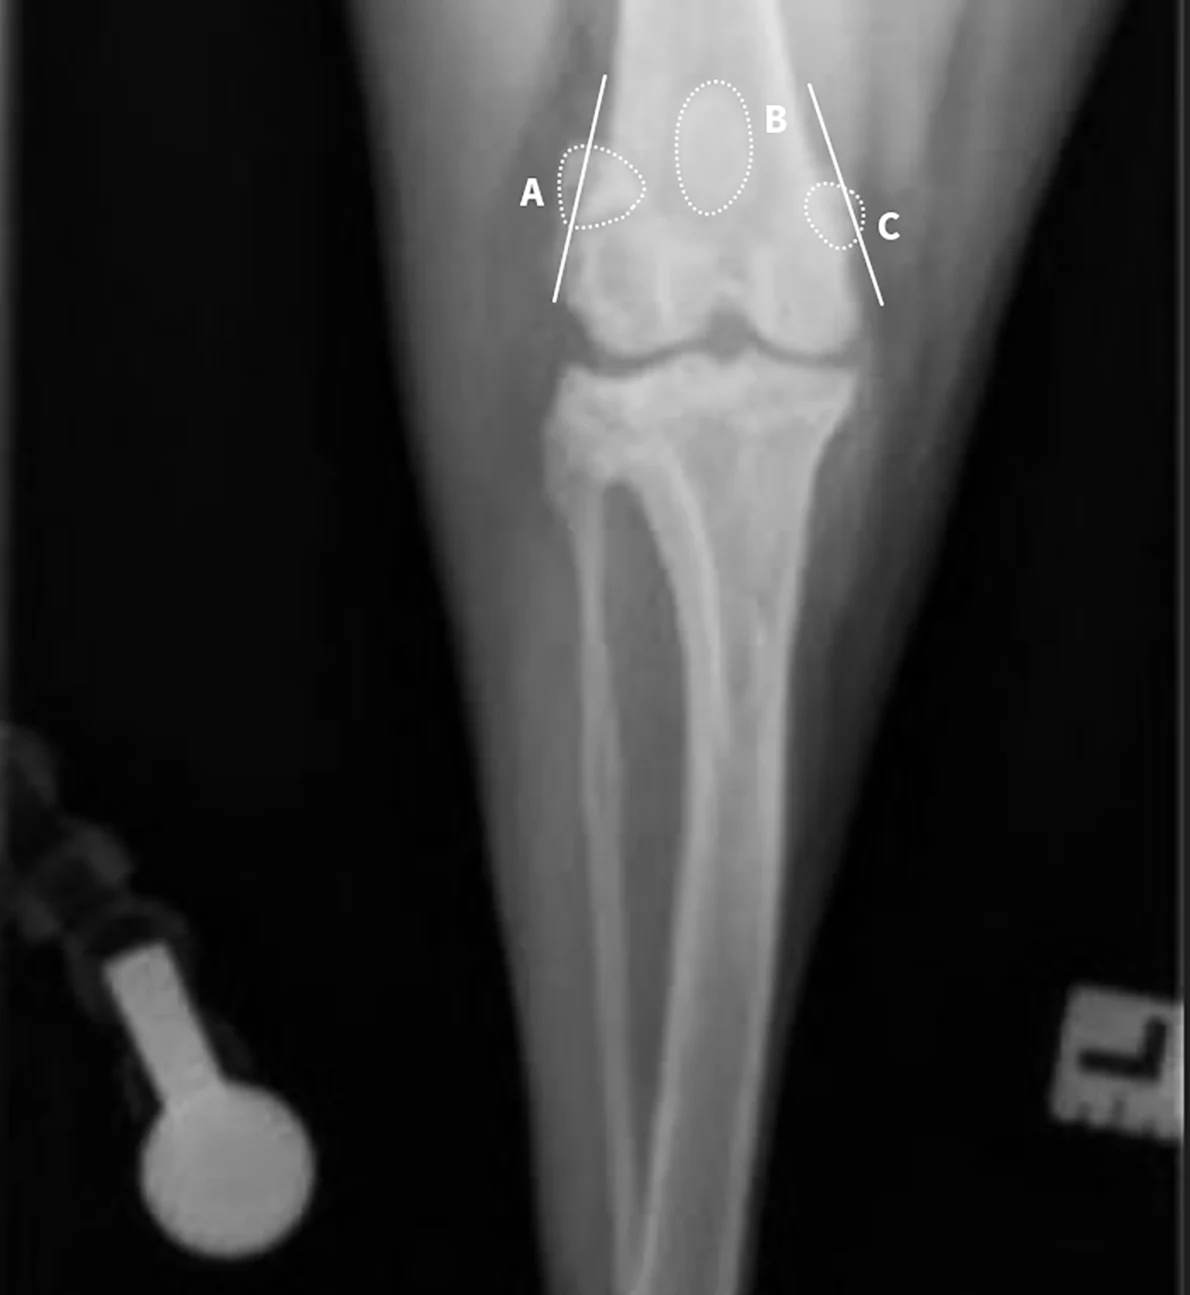

Place the patient in dorsal recumbency (or for caudocranial projection, position the patient in sternal recumbency). Center the abdomen over a V-trough sponge positioner to keep the body straight; ensure the pelvis and caudal abdomen are outside of the trough. Retract the pelvic limb caudally, pulling the hips and stifles into full extension; manually hold (or tape) the limb in position. Once the pelvic limb is completely extended, rotate the stifles slightly medially to align the stifle joints. Center the patella within the patellar groove, facing toward the ceiling.

Center the collimator beam over the tibia to include the stifle and tarsal joints. Ensure the beam is extended laterally to just outside the margins of the skin.

Author Insight

On the radiograph, the medial (A) and lateral (C) fabellae should be bisected by the medial and lateral femoral cortices (lines). The patella (B) should be centered in the patellar groove. The medial edge of the calcaneus (arrow) should bisect the distal intermediate ridge of the tibia (center of the curved line), ensuring a straight tarsus and distal tibia. If the stifle and tarsus (circles) are straight, the tibia and fibula will be straight. In the rare case of an angular or torsional deformity, achieving a straight view of the stifle and tarsus in 1 view may be challenging; straight views of the stifle and tarsus should thus be acquired individually.